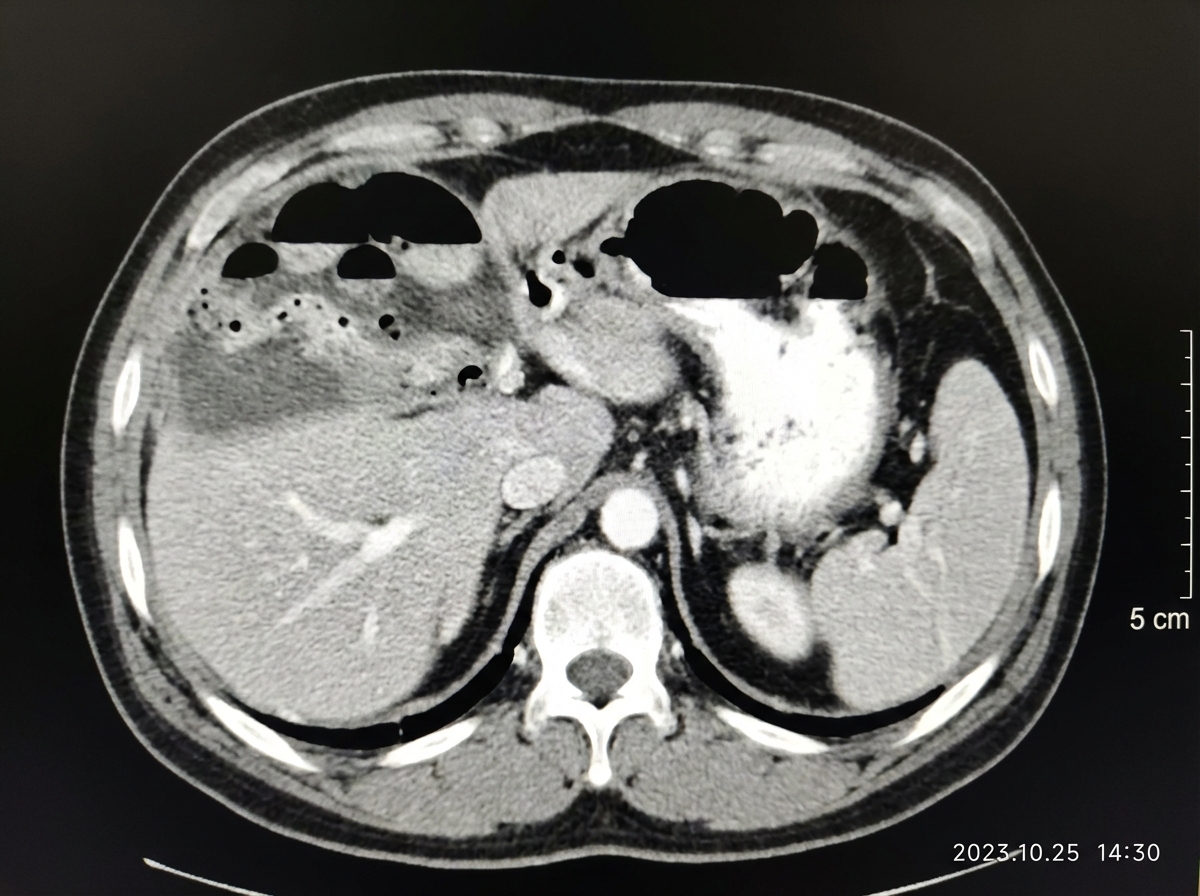

A patient after abdominal surgery presents with fever, chills, rigors along with pain in right hypochondrium, right shoulder along with Hoover's sign. Abdominal CT of the patient is given. What is the most likely diagnosis?

Explanation: ***Subphrenic abscess*** - The CT scan shows a **fluid collection (abscess)** with a septated appearance located beneath the diaphragm, consistent with a **subphrenic abscess** - **Hoover's sign** (inspiratory lag of the affected hemidiaphragm) is pathognomonic for subphrenic pathology - **Referred shoulder pain** occurs due to diaphragmatic irritation transmitted via the phrenic nerve (C3, C4, C5 - "keeps the diaphragm alive") - Classic post-operative complication following **abdominal surgery**, especially upper abdominal procedures - CT shows characteristic **subdiaphragmatic location** with gas-fluid level *Liver abscess* - Would present with hepatomegaly and tender liver on examination - CT would show an **intraparenchymal liver lesion**, not a subdiaphragmatic collection - Does not typically cause Hoover's sign or diaphragmatic involvement *Acute cholecystitis* - Presents with **Murphy's sign**, not Hoover's sign - CT would show **gallbladder wall thickening, pericholecystic fluid**, not a subdiaphragmatic collection - Shoulder pain less prominent; typically right subscapular pain *Right lower lobe pneumonia* - Would show **pulmonary infiltrates** on imaging, not an intra-abdominal fluid collection - Respiratory symptoms (cough, dyspnea) would be more prominent - Does not explain the abdominal CT findings showing subdiaphragmatic collection